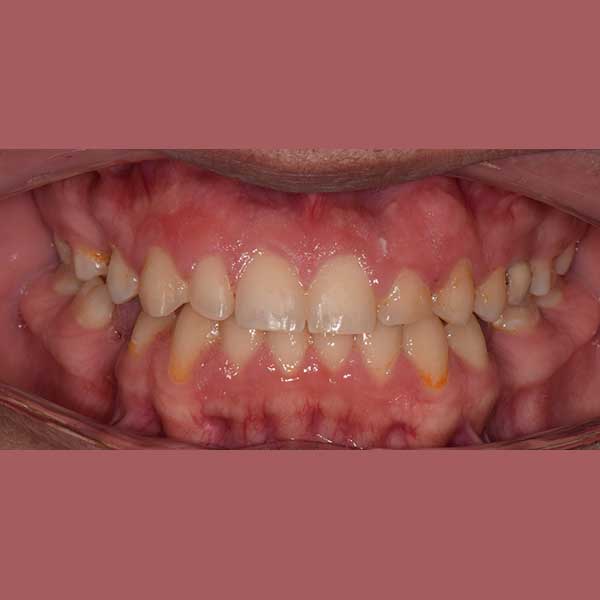

BEFORE

My friend here has suffered from the early loss of some permanent back teeth, which led to the creation of spaces between the front teeth and the inability to place dental implants to replace the missing teeth due to the small spaces between the front teeth.